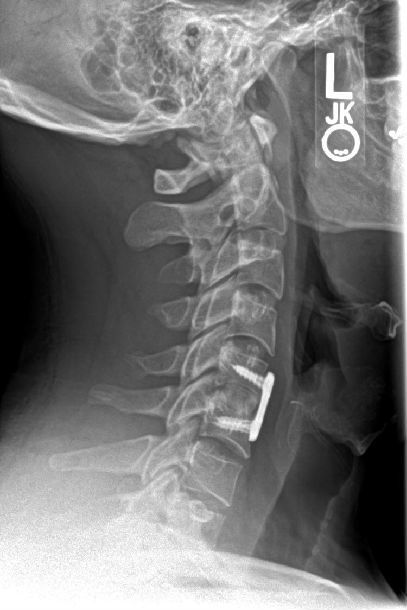

完成颈椎前路显微镜手术的患者X光